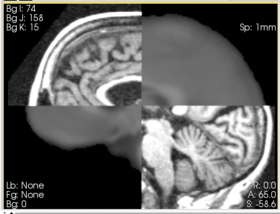

In this short tutorial, we will show how the Affine Registration module can be used to register two images from different subjects. The data is from the Oasis Brains project and the [http://www.loni.ucla.edu/Atlases/Atlas_Detail.jsp?atlas_id=6 ICBM. We will be registering the volumes icbm452_atlas_air12_sinc.hdr and OAS1_0001_MR1_mpr-1_anon.hdr. Be sure to load the volumes with the "Centered" option checked. Rotation is performed around the center, and a centered volume usually produces a more robust result.

Set the Fixed image to icbm452_atlas_air12_sinc.hdr and the moving image to OAS1_0001_MR1_mpr-1_anon.hdr. The default settings are sufficient to register these images

In this short tutorial, we will show how the Affine Registration module can be used to register two images from different subjects. The data is from the Oasis Brains project and the [http://www.loni.ucla.edu/Atlases/Atlas_Detail.jsp?atlas_id=6 ICBM. We will be registering the volumes icbm452_atlas_air12_sinc.hdr and OAS1_0001_MR1_mpr-1_anon.hdr. Be sure to load the volumes with the "Centered" option checked. Rotation is performed around the center, and a centered volume usually produces a more robust result.

Set the Fixed image to icbm452_atlas_air12_sinc.hdr and the moving image to OAS1_0001_MR1_mpr-1_anon.hdr. The default settings are sufficient to register these images